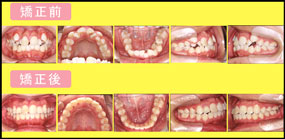

@ガタガタ

歯ならびがガタガタで・・・

口を大きくあけて笑えなくって・・・

<歯を抜かないで治しています>

主訴:ガタガタが気になる

診断名主な症状:Class II crowding

開始年齢:10

装置:H.G+M..B.S.

抜歯部位:非抜歯(0本)

治療期間:26ヵ月

治療費:52万+消費税

リスク(カリエス・歯周病・歯根吸収):矯正治療中・後カリエス等無し